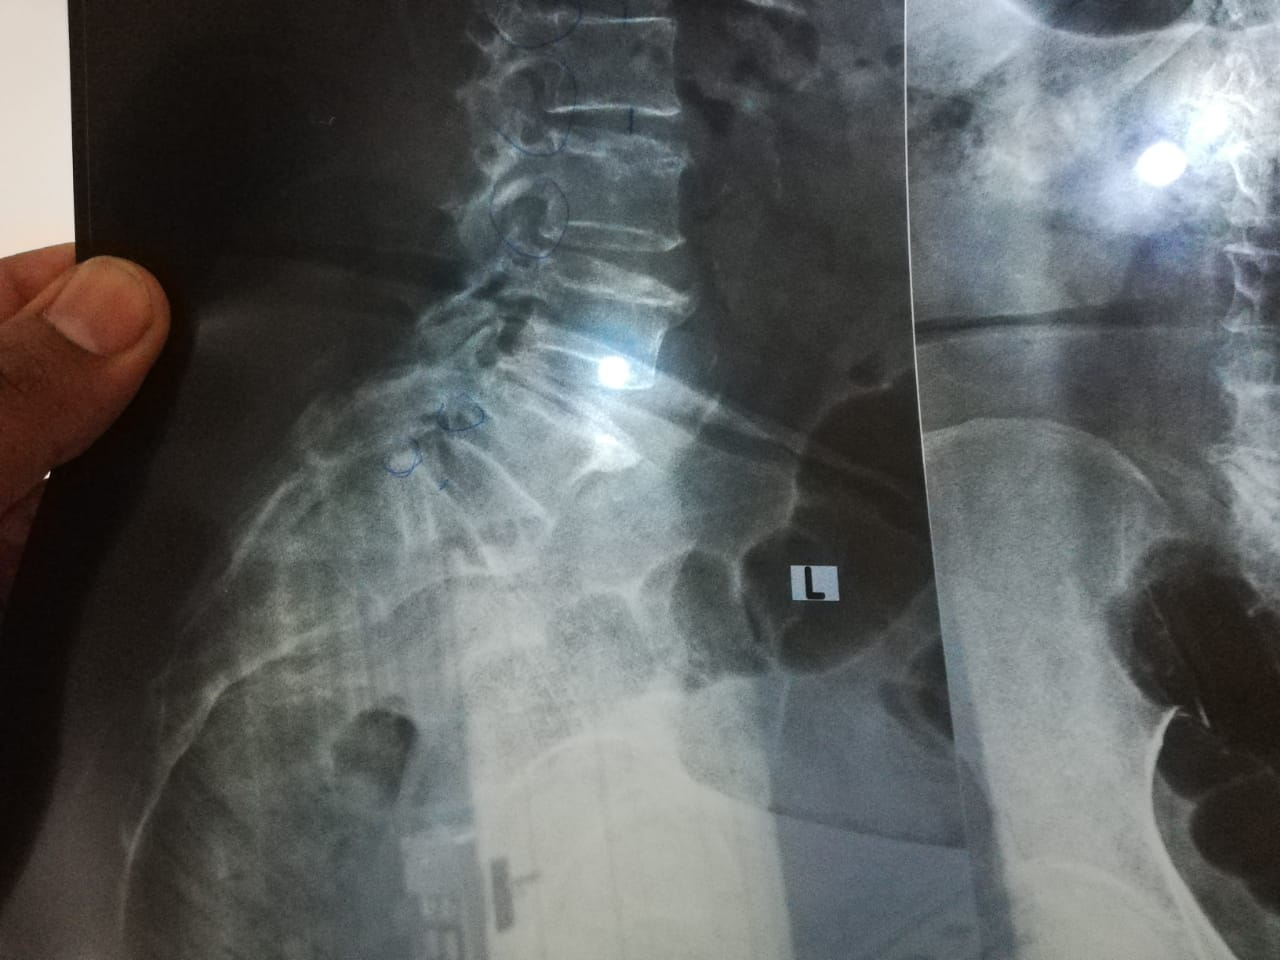

My mother is Diabetic (on inj insulin), hypertensive, and Stage 2 renal failure all are under control (as she taking medicine regularly). Since last 2-3 weeks, She developed lower back pain radiating to left leg. Pain is sharp, periodic, more sever when she moves or sits, relieves by lying flat on bed or if if keeps sleeping. Need to know what are best options for her. Invasive and non-invasive. Thanks in advance.

We've done MRI and it shows compressed nerve roots at level L4, L5 levels with decreased disc space. Gabapil is not helping much. We went to a pain management doctor. And he is suggesting laser nerve root therapy for 50K. People say laser is not standard treatment. Can u comment on it ? Thanks

Disc space narrowing is causing compression of nerves. Treatment options include medicines, physiotherapy, or surgery. Since there are other comorbid conditions also, a pain clinic would be an exact place to visit for further evaluation and expert management